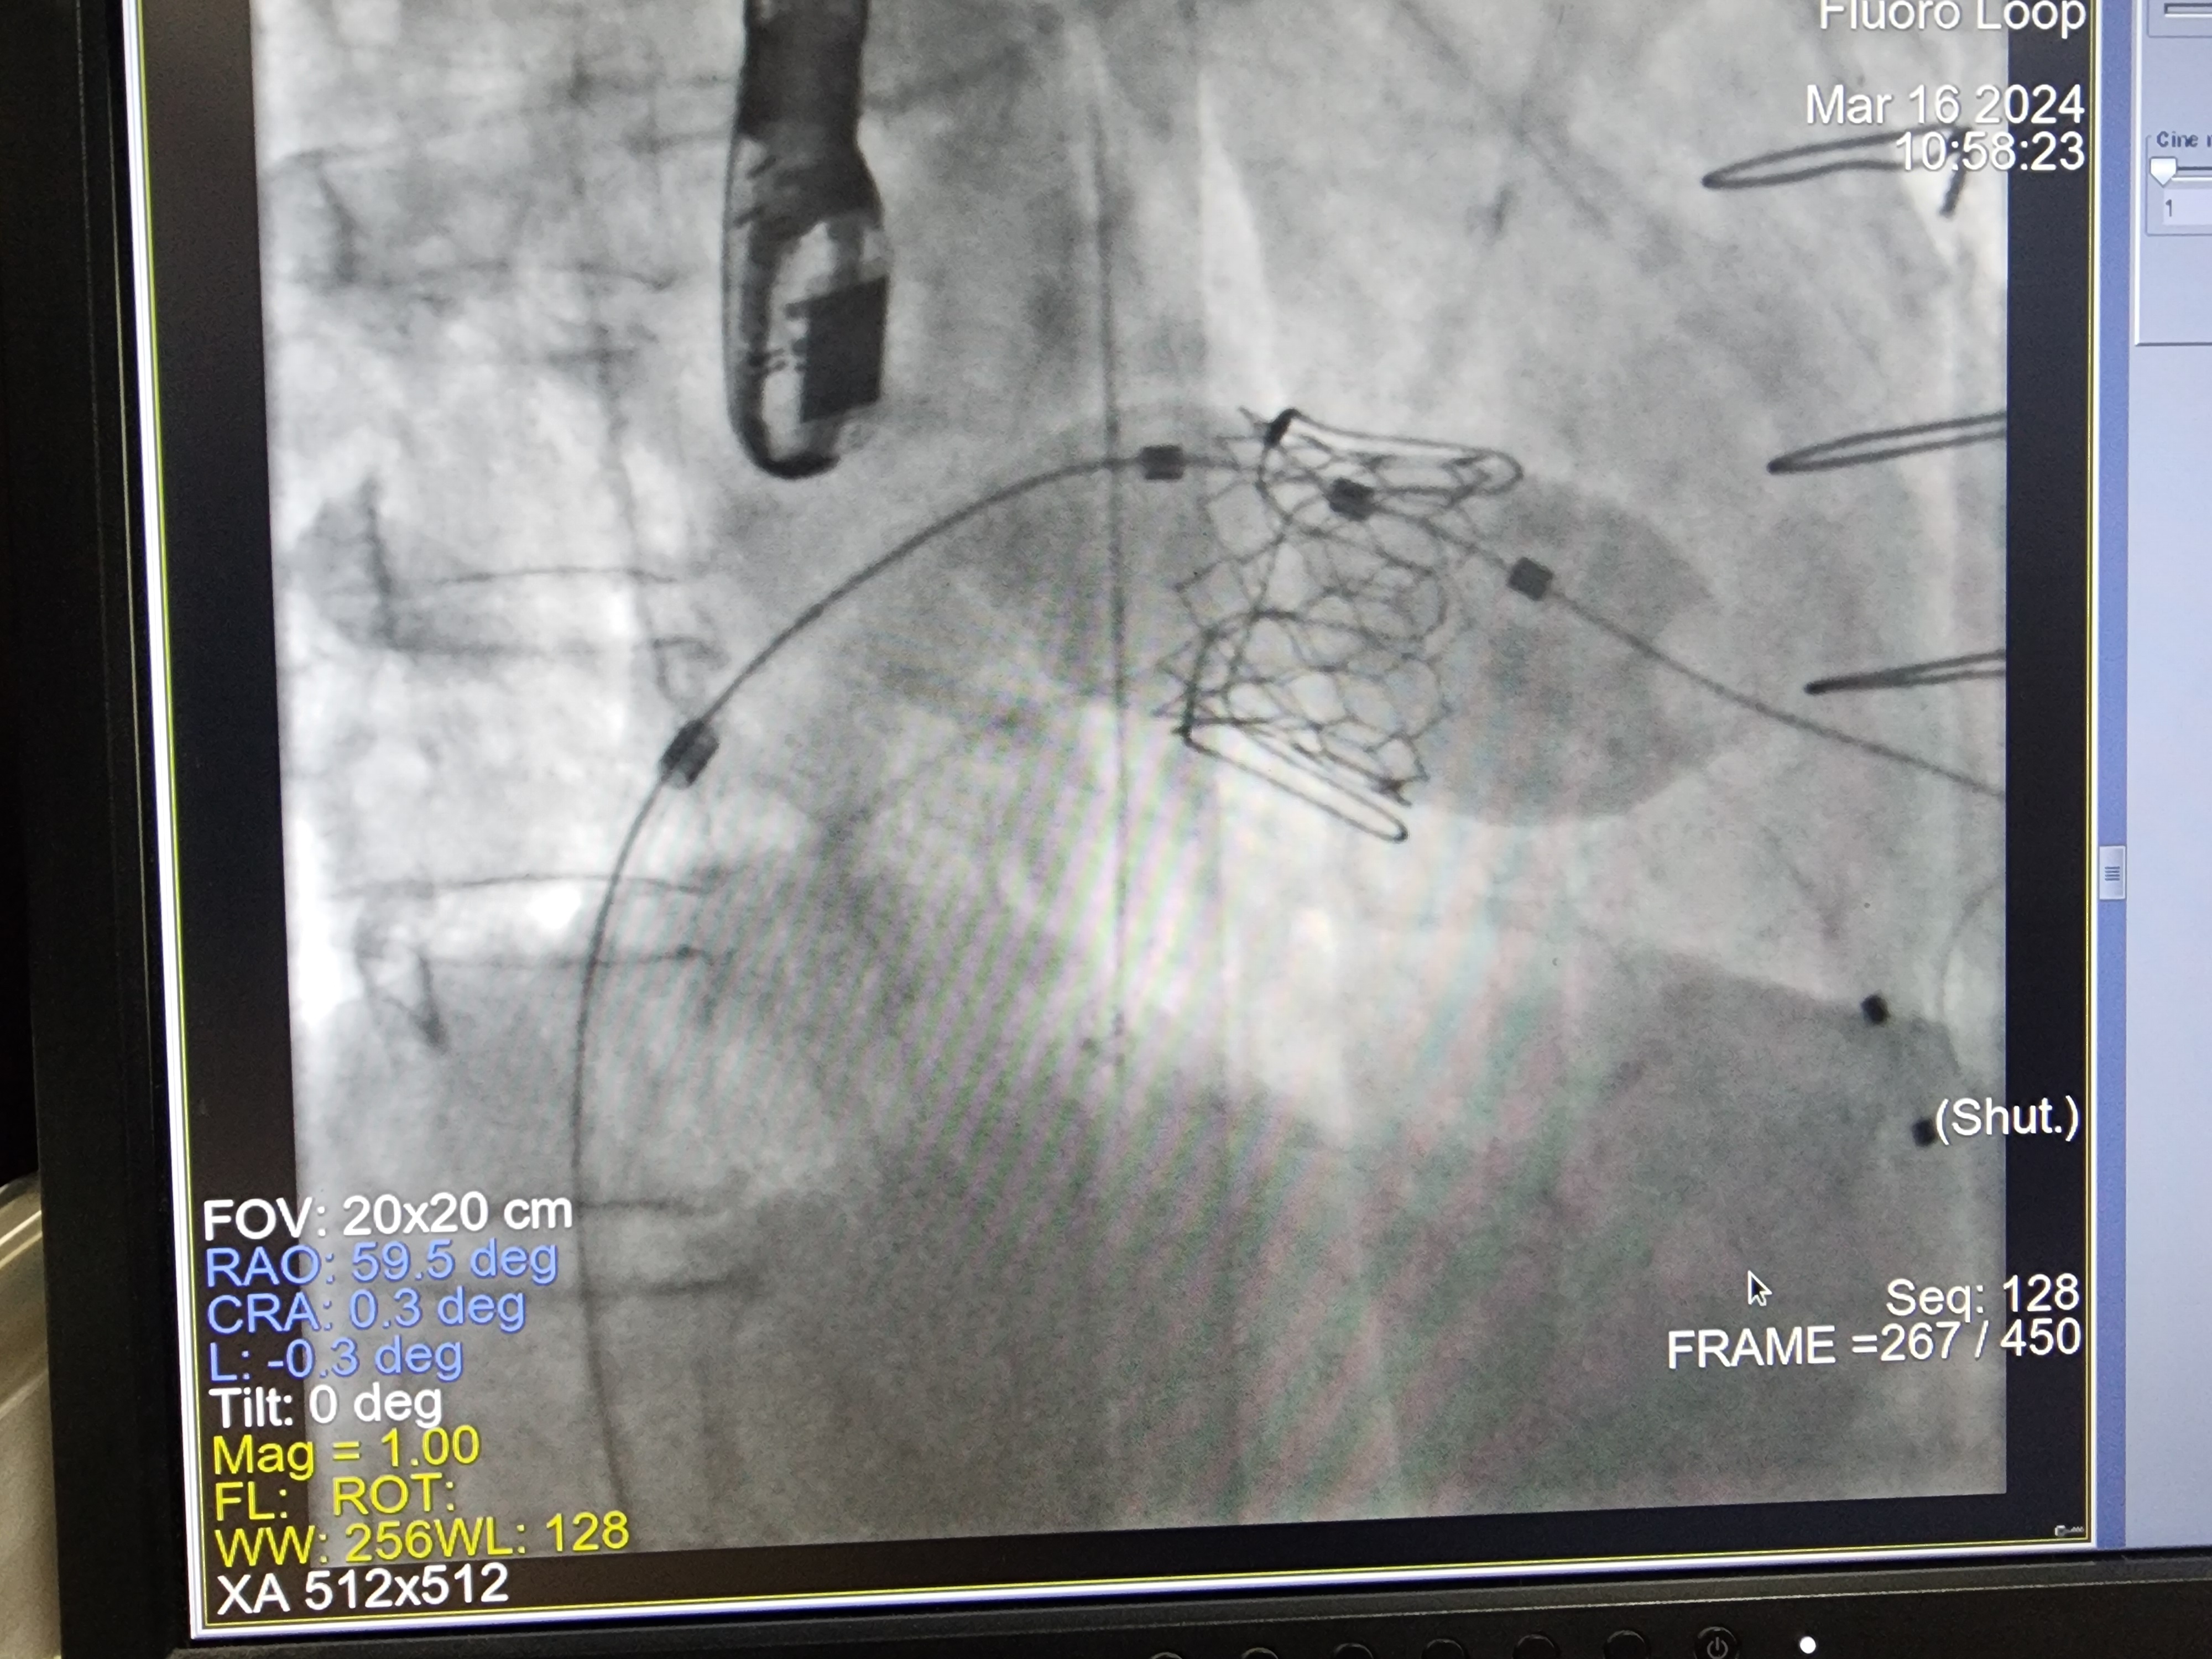

The Transcatheter Mitral Valve in Valve Replacement (TMVIR) was then successfully performed using a 26-mm Myval¢â transcatheter heart valve. This was carried out under rapid pacing at 180 bpm.

"TMVR is a vital therapeutic option for high-risk, inoperable patients with severe mitral disease. However, displacement of the native anterior mitral leaflet toward the interventricular septum can cause acute LVOT obstruction, a common complication with high mortality. Predicting and preventing this is essential.

LAMPOON is a transcatheter electrosurgical technique designed to split the anterior mitral valve leaflet immediately prior to TMVR, preventing this obstruction. It is a novel, life-saving therapy."